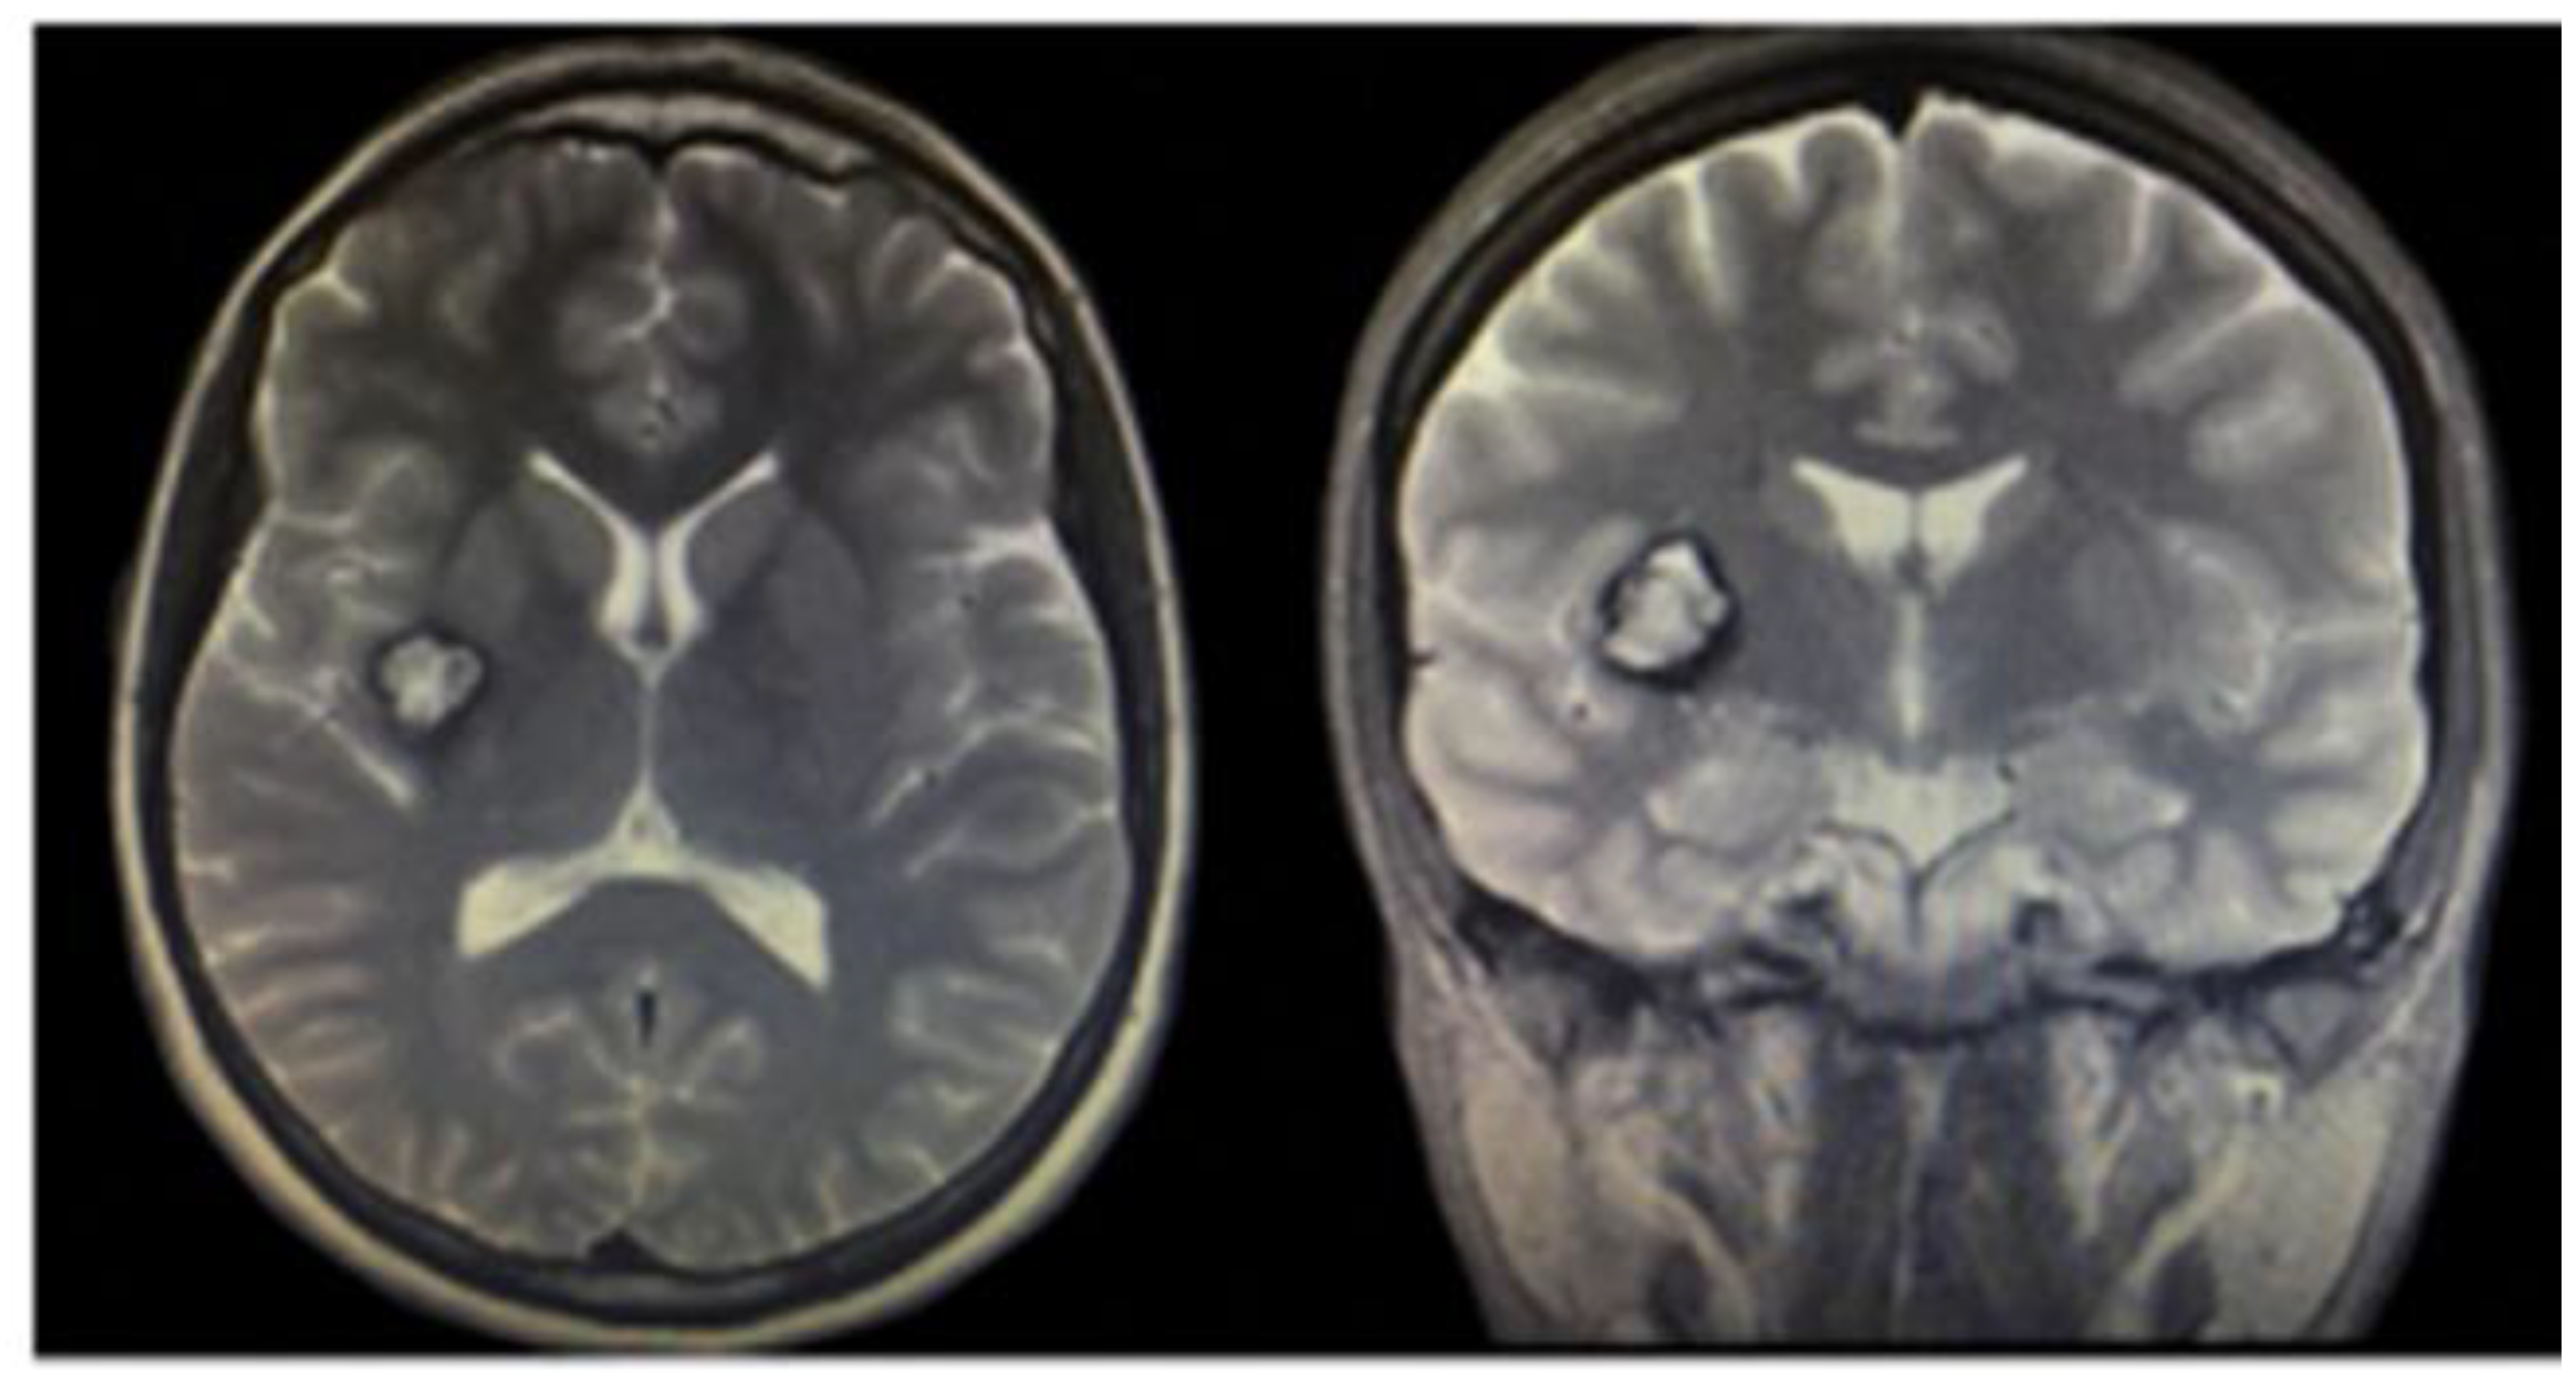

3.1.2. Brain Cavernous Angiomas

- Mokin, M.; Agazzi, S.; Dawson, L.; Primiani, C.T. Neuroimaging of Cavernous Malformations. Curr. Pain Headache Rep. 2017, 21, 47. [Google Scholar] [CrossRef]

- Hassani, F.D.; Karekezi, C.; El Abbadi, N. Rare Case of Giant Pediatric Cavernous Angioma of the Temporal Lobe: A Case Report and Review of the Literature. Surg. Neurol. Int. 2020, 11, 7. [Google Scholar] [CrossRef] [PubMed]